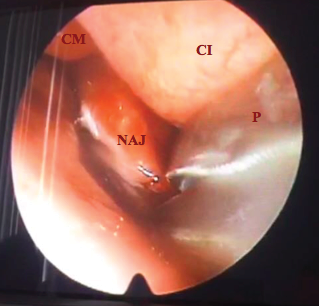

En el consultorio se realizó nasofibrolaringoscopia observándose masa pálida dependiente del cornete medio izquierdo en alto contacto con el cornete inferior izquierdo (Figura 4)

![NAJ Nasoangiofibroma Juvenil. CI[Cornete inferior]](../273856494018_gf6.png)